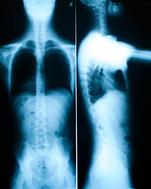

Weight bearing X-rays will be taken unless special circumstances exist (such as pregnant women or young children/infants) for the area of complaint. These are necessary for several reasons. It is used to determine the health of the disc that sits between each vertebrae in the spine. It also shows us signs of degenerative changes and shows us potential problem areas along the spine. X-ray can also rule out or identify any potential pathology (diseases) or other health concerns. Lastly, X-ray helps the doctor give a more specific adjustment as he caters the adjustment to your spine. No persons spine is the same as the next persons so an X-ray aids in making sure the doctor can give a specific chiropractic adjustment.